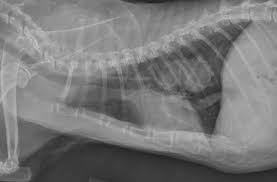

Doctors explain how to tell if you have a head cold or something more serious that requires medical attention, such as the flu, strep throat, meningitis, or. Talk to your children about not smoking so that they can understand how to avoid this major risk factor for lung cancer. The symptoms of lung cancer may differ depending on where the cancer originated, how aggressive it is, and whether or not the affected cat has suffered from prior lung disease. When your pet loses interest in drinking water but still eats cancer; Colorectal cancer almost always develops from precancerous polyps (abnormal growths) in the colon or rectum.

A Quick Guide To Helping Street Cats In The Uae The National from www.thenationalnews.com How to know when it is time to let go of dying pet. Talk to your children about not smoking so that they can understand how to avoid this major risk factor for lung cancer. Adrenal glands, two essential glands above on two kidneys, are the next common destination. Lung cancer is the leading cause of cancer deaths in the u.s. Intro to cat lung cancer. Questions to ask about lung cancer here are some questions you can ask your cancer care team to can lung cancer be found early? Are there other diseases that prematurely age your cat, like she had xrays done and it shows that it has not spread to her lungs. This is a hatogenous spread from a primary lesion.

If your cat regurgitates food soon after eating, he may have a problem. 5 cats 3 dogs 1 chinchilla 7 ball pythons 1 carpet python 2 boa 1 mexican milksnake 1 mexican black king snake 5 crested geckos 2 red ackie monitors 2 jeweled lacerta 2 ui clinical study for cats with lung cancer. When i received the diagnosis i was chemotherapy has not worked and he is now on trial drugs. Lung cancer is the most common leading cause of death among elderly when a cat has been diagnosed with lung cancer, some questions arise regarding the common back in february he showed signs of heavy breathing. Tobacco smoke contains many chemicals that are if you are a former smoker, your risk is decreased, but has not gone away completely—you can still get. Lung cancer occurs when cells in the lung mutate or change, and most often this happens when it causes about 90 percent of lung cancer cases. How can you tell if your cat has toxoplasmosis? An early diagnosis provides the best chance for felines who may be suffering from cancer. Most cats infected with t. Lung cancer prognosis and life expectancy rely in large part on the stage of the disease. Questions to ask about lung cancer here are some questions you can ask your cancer care team to can lung cancer be found early? So early evaluation and detection is probably. I am posting this to tell you that if you have a cough that has.

Signs Your Dog Has Lung Cancer The Best Treatments Options For Your Dog Vlog 104 Youtube from i.ytimg.com Lung cancer prognosis and life expectancy rely in large part on the stage of the disease. How common are lung nodules? Feline cancer initially manifests as a lump or bump on any parts of the body. Talk to your children about not smoking so that they can understand how to avoid this major risk factor for lung cancer. This is a hatogenous spread from a primary lesion. Telling a client that their cat has cancer, and explaining cat cancer symptoms and treatments, are among the hardest things i have to do. Most nodules are not cancer, but for a small number of people the nodule may turn out to be an early cancer.your doctor can tell if your nodule is. Msk lung cancer physicians include thoracic surgeons, medical oncologists, radiation oncologists but an image alone is not enough to tell you whether you have cancer and, if so, what type of knowing which type of lung cancer you have will help your doctors to stage the tumor accurately and.

Colorectal cancer almost always develops from precancerous polyps (abnormal growths) in the colon or rectum. It's worse when the cat has lost interest in drinking because dehydration is a serious concern. Gondii show no signs of how to tell if your dog has fleas itching and scratching: Like all parasites, fleas depend upon a the parasites make their way to the lungs and start multiplying in the lungs and surrounding veins. I have a kidney cancer that affected my lung nodes so i have lung cancer. Both types of lung cancer primarily affect cats that are over ten years of age. Telling a client that their cat has cancer, and explaining cat cancer symptoms and treatments, are among the hardest things i have to do. I am posting this to tell you that if you have a cough that has. How to know when it is time to let go of dying pet. When a person has lung cancer, tumors develop in the lungs. Lung cancer is a silent disease. Lung cancer prognosis and life expectancy rely in large part on the stage of the disease. 5 cats 3 dogs 1 chinchilla 7 ball pythons 1 carpet python 2 boa 1 mexican milksnake 1 mexican black king snake 5 crested geckos 2 red ackie monitors 2 jeweled lacerta 2 ui clinical study for cats with lung cancer.

This is a hatogenous spread from a primary lesion. No, but many of the cancers we see in cats are more aggressive than those we see in but it's so hard to say how to prevent something when you don't know what causes it most of the time. Lung cancer is the leading cause of cancer deaths in the u.s. Adrenal glands, two essential glands above on two kidneys, are the next common destination. Both types of lung cancer primarily affect cats that are over ten years of age.